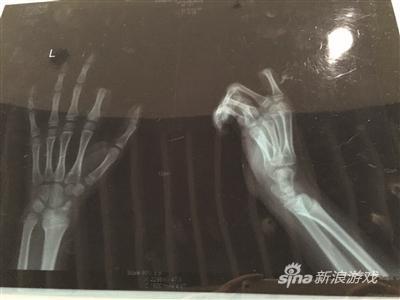

X光片显示孩子食指两个指节被切断X光片显示孩子食指两个指节被切断

不一会儿,饭做好了,听见这段对话的邹某,已经对小朋一直玩游戏的状态有些不满,便忍不住对小朋训斥了几句。当时,小朋手里正拿着叉子在叉土豆泥吃,听了爸爸训斥的话后,立马就炸毛了,放下手中的叉子,转身就拿起了身后矮桌上的菜刀,朝着自己的左手切下去,当场,食指的两个指节就掉了下来。

手术历经3个多小时。若能顺利度过一个星期的危险期,接上去的手指便能成活。苏州大学附属瑞华医院手外科主任周荣是小朋的主刀医生。下午1点不到,小朋便被推进手术室做准备,下午4点左右,小朋才被推出了手术室,转入病房。不幸中的万幸,经过三个多小时的手术,小朋的手指被暂时接上。